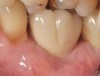

The crown and screw-retained custom abutment were removed, and a surgical cover screw was placed into the implant, thereby allowing spontaneous gingival augmentation in situ (Figure 33 and Figure 34). Note that the lingual aspect of the implant site was significantly more coronal than the labial aspect, which was positive because the defect would be limited to a facial–lingual defect. A fixed RBR bridge was cemented on the adjacent teeth and used as a tooth-supported transitional provisional restoration (Figure 35). A few weeks were allotted to let the soft tissue heal and migrate around the cover screw (Figure 36) to see if there would be complete coverage, thereby allowing a soft-tissue augmentation procedure to be performed with primary flap closure as in clinical scenario No. 2. The major obstacle in achieving a positive tissue response was that the implant depth was also deficient because the implant–abutment connection was at the level of the free gingival margin. It was decided that the best treatment option would be to remove the implant. A high-powered reverse-torque device (Fixture Remover Kit, NeoBiotech, www.neobiotechus.com) was used to remove the implant atraumatically (Figure 38 through Figure 41). The implant socket was allowed to heal for several months not unlike an extracted tooth (Figure 42). A new implant was placed in a better position from both a restorative and esthetic perspective (Figure 43), and after a few months of healing, a new crown was made (Figure 44). A satisfactory functional and esthetic result was achieved (Figure 45 and Figure 46) without employing pink porcelain.

Fig 35. A transitional resin-bonded-retained (RBR) bridge that was tooth supported was placed to allow soft-tissue maturation.

Figure 35

Fig 36. Two weeks after RBR placement, the soft tissue did not adequately cover the implant. The problem was in poor implant angulation and proper depth to allow the soft tissues to cover over.

Figure 36